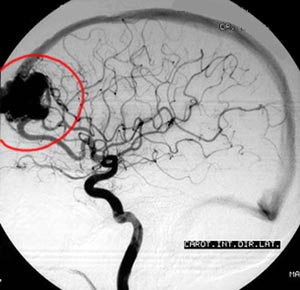

2c) Malformação arteriovenosa (MAV)

Figura 49 - Angiografia cerebral antes da cirurgia.